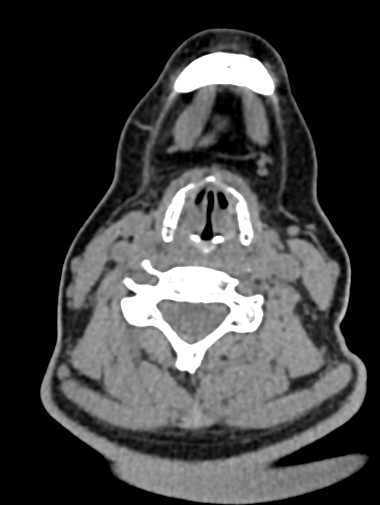

Функциональные пробы подразумевают проведение КТ гортани в трех режимах:

- Пациент делает небольшой вдох, при этом получается КТ- изображение голосовых складок в положении их наибольшего расхождения, что позволяет оценить степень их подвижности и ширину голосовой щели.

- Пациент произносит звук «и». Проба во время фонации позволяет оценить состояние голосовых складок в положении их наибольшего сближения.

- При необходимости проводится проба Вальсальвы (пациент делает глубокий вдох, зажимает нос и рот и делает выдох в носоглотку). Благодаря этому повышается давление в носоглотке и происходит раскрытие грушевидных синусов (пространства в боковых отделах гортани).